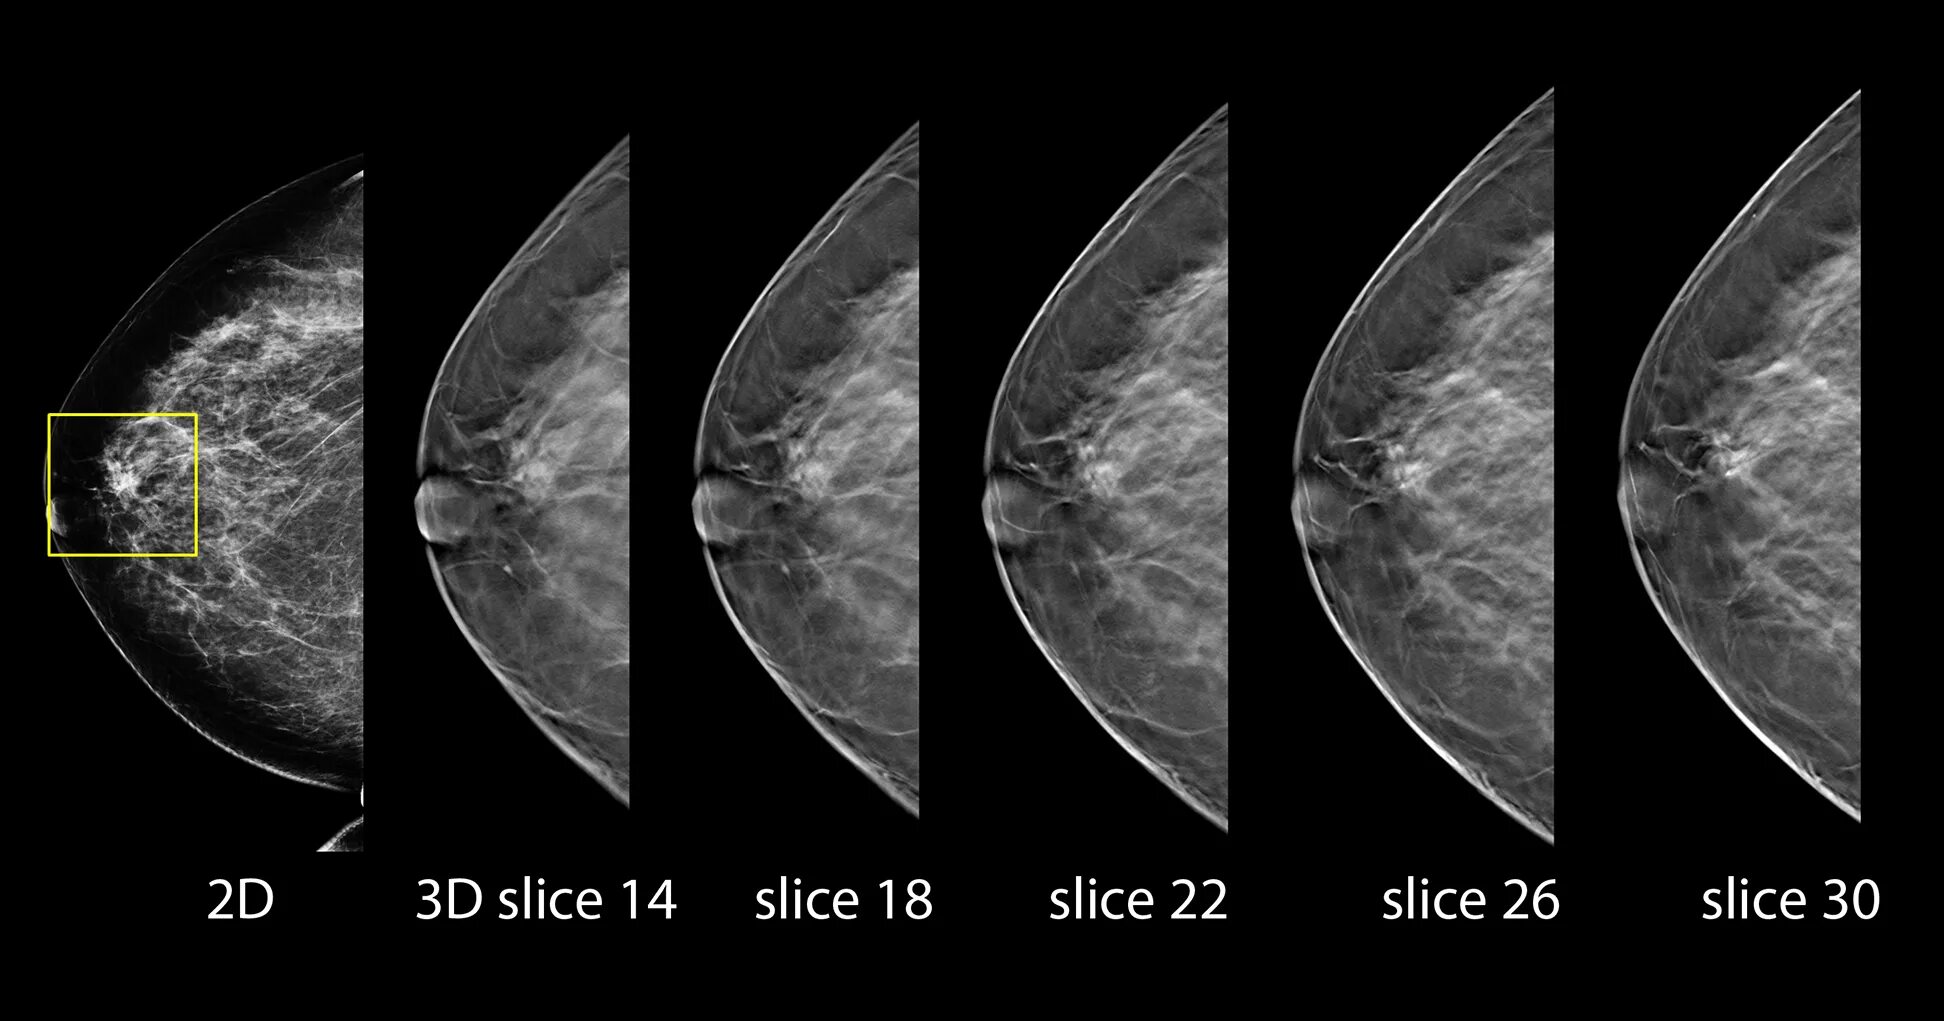

Делают ли кт молочных желез